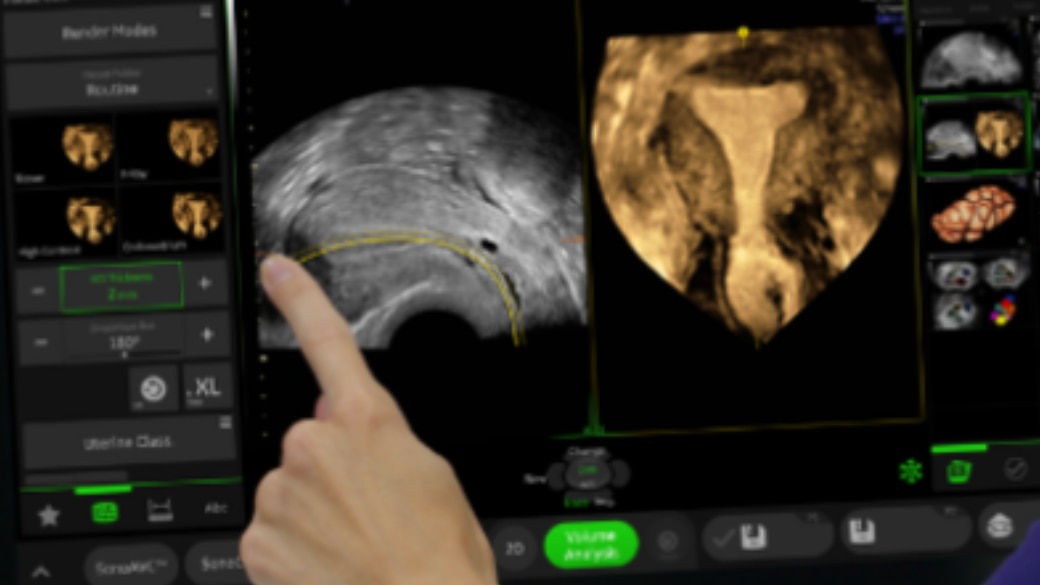

Voluson™ Graphicflow

Visualize trajectories of fetal blood cells in real-time

Provides a graphical representation of the trajectories of the blood cells in real-time to visualize complex blood flow quickly and clearly, helping to differentiate normal from abnormal hemodynamics especially in fetal heart and fetal brain.